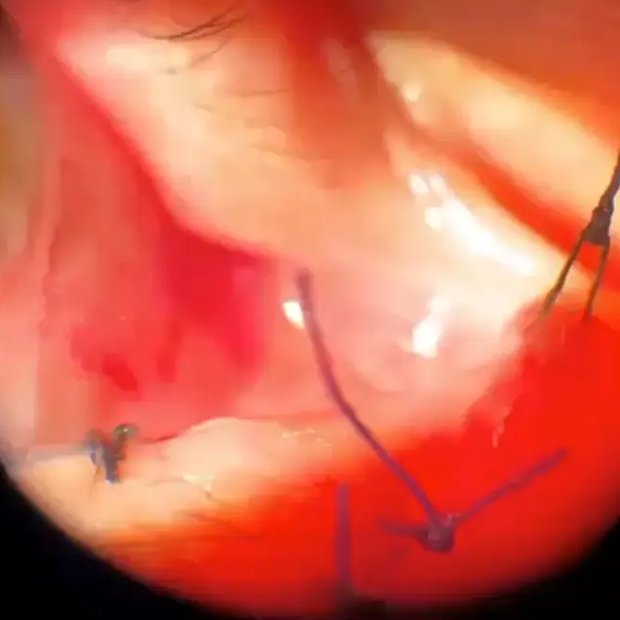

VPP con explante de LIO, Artisan retropupilar y F…

José Gegúndez, Mercedes Molero, Sara Garcia Caride